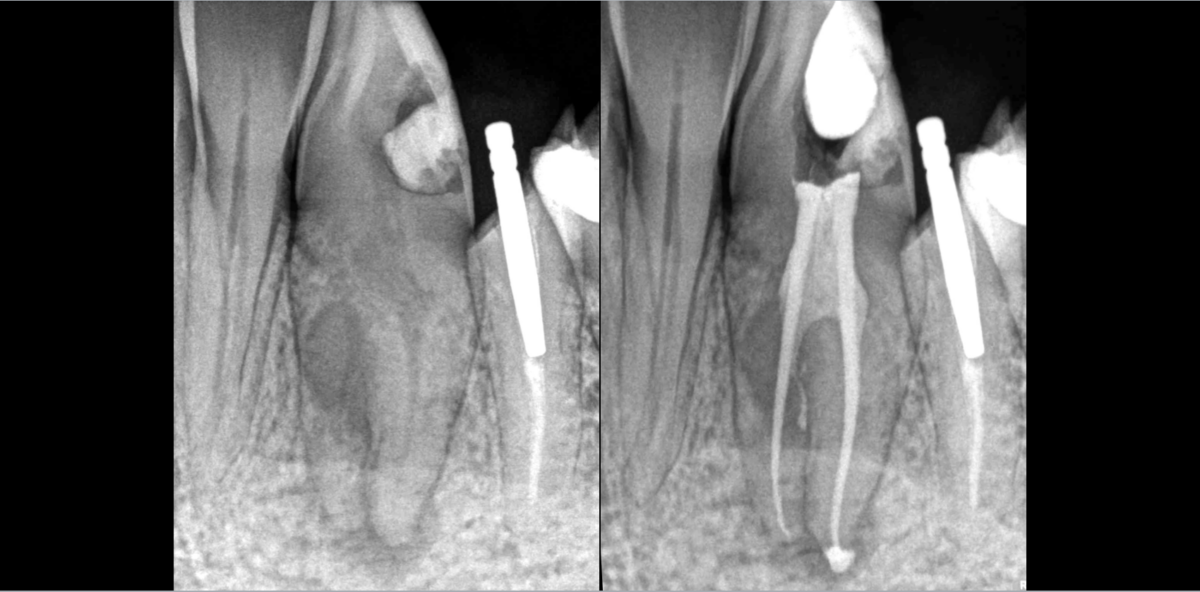

Cette canine à 2 canaux.

🦷 Complètement en rotation à 90°, elle nous empêche d’accéder en palatin.

✅ Cavité d’accès réalisée par abord vestibulaire.